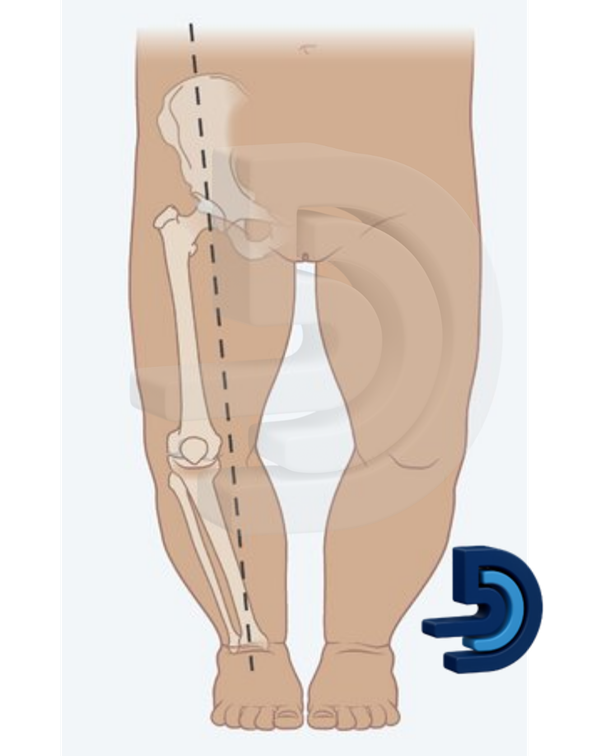

Çocuğumun bacakları parantez gibi, düzelir mi? Çocuğunuz ayakta durduğunda ya da yürürken bacaklarının parantez şeklinde göründüğünü fark ettiyseniz, bu durum…